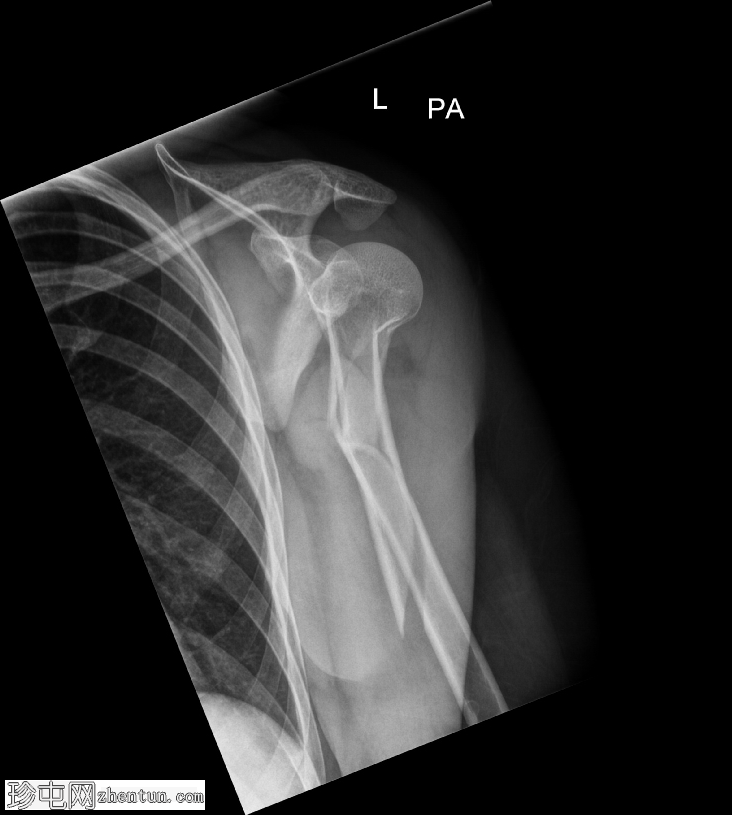

正位

肱骨近端粉碎性移位骨折,累及骨干近端半部、外科颈,并延伸至大结节。

肱骨头在肩关节内向下半脱位,肩峰肱骨间距增大。

肱骨头向下移位(假性半脱位)是肱骨近端骨折常见的继发性表现。它提示关节积液、关节积血或暂时性关节囊松弛,而非肩关节真正的不稳。手臂负重和肌肉张力下降(尤其是三角肌和肩袖肌群)共同导致肱骨头相对于肩胛盂位置下移<sup>1-3</sup>。

这种表现不应与真正的肩关节脱位混淆,因为在Y形位或轴位影像上,肱骨头仍与肩胛盂保持正确的对位。随着关节液的吸收和肌肉张力的恢复,这种情况通常会自行缓解。识别这种暂时性的良性表现对于避免不必要的复位手术至关重要。

在本病例中,肱骨头位置下移反映了由急性近端肱骨骨折引起的关节积液所致的假性半脱位,而没有真正的脱位证据。